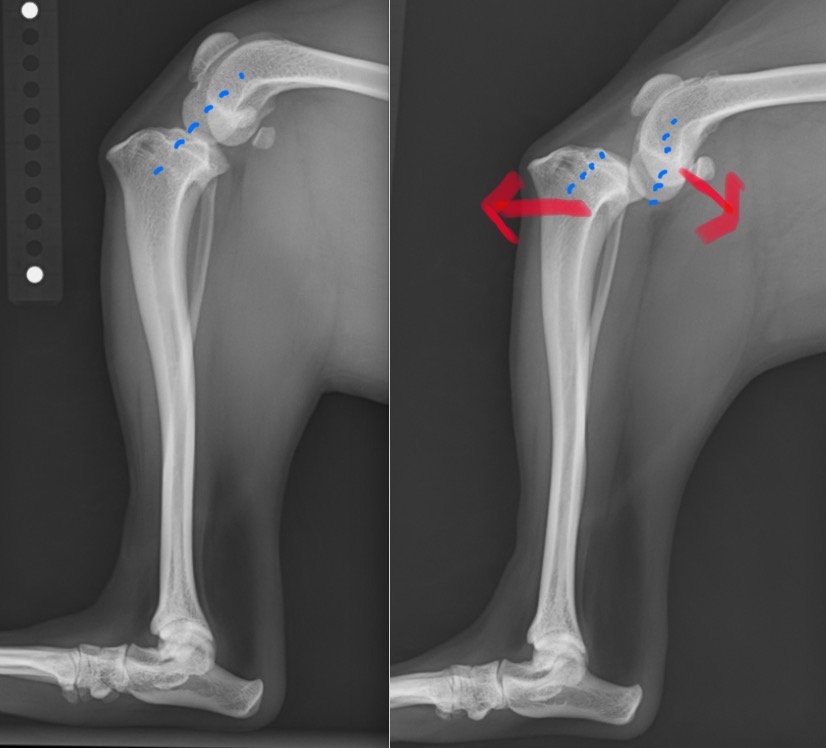

前十字靭帯が損傷すると膝関節が不安定になり、ももの骨とすねの骨が前後にずれるような状態になります。

これによりうまく体重を支えられなくなり、多くの子は足を着けなくなってしまいます。

左:正常膝関節 / 右:前十字靭帯を損傷し不安定性が見られる膝関節